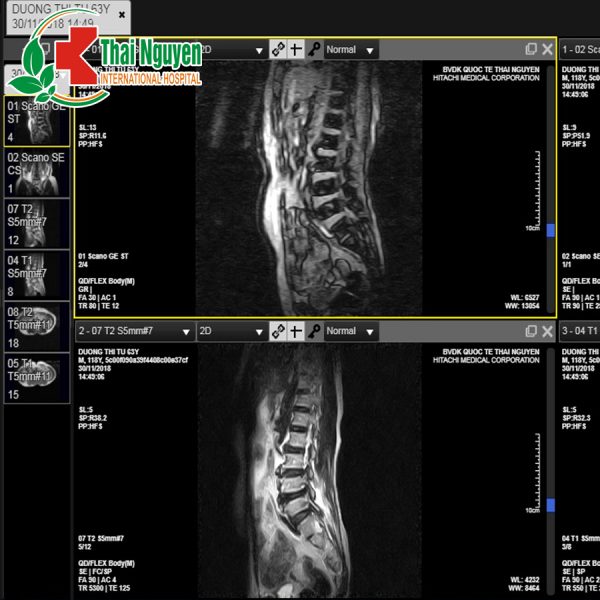

TRIỂN KHAI ĐỀ ÁN BỆNH VIỆN KHÔNG PHIM VỚI CÔNG NGHỆ PMR PACS TẠI BỆNH VIỆN QUỐC TẾ THÁI NGUYÊN

Kể từ tháng 12/2018, BVQTTN chính thức đưa vào sử dụng công nghệ xử lý hình ảnh PMR PACS  hỗ trợ công tác chẩn đoán hình ảnh.

Bệnh nhân đến viện thăm khám trong đa số trường hợp sẽ KHÔNG CẦN IN PHIM CHỤP như quy trình khám bệnh truyền thống. Các y bác sĩ trực tiếp đọc phim, hội chẩn hoàn toàn ONLINE dựa trên nền tảng điện toán đám mây, giảm tối đa thời gian, chi phí cho người bệnh. BVQTTN là một trong những đơn vị đầu tiên tại địa bàn tỉnh Thái Nguyên nói riêng và cả nước nói chung đi tiên phong trong việc ứng dùng công nghệ thông tin vào công tác khám chữa bệnh.

Công nghệ PMR PACS là một công nghệ xử lý hình ảnh y tế mang đến giải pháp lưu trữ kinh tế và sự thuận tiện trong truy cập vào các hình ảnh từ nhiều máy chụp chiếu khác nhau. Hình ảnh và báo cáo điện tử được truyền dưới dạng số hóa qua PACS giúp loại bỏ việc phải làm thủ công các công việc như lập hồ sơ, tìm kiếm, vận chuyển phim chụp, các File chuyên dụng để lưu trữ và bảo vệ phim X quang.